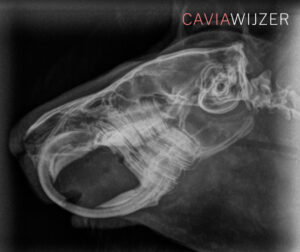

Een caviadierenarts doet bij iedere controle een gebitsinfectie met behulp van een otoscoop. Dit is een medisch instrument waarmee artsen normaal gesproken de binnenkant van het oor bekijken. Het is ook geschikt om het caviagebit te inspecteren op afwijkingen. De cavia hoeft hiervoor niet onder narcose. Helaas zijn niet alle gebitsafwijkingen op deze manier te zien. Voor het opsporen van problemen in de kaak of kieswortels is een röntgenfoto noodzakelijk. Ook hiervoor hoeft de cavia niet onder narcose. Het beoordelen van röntgenfoto’s op gebitsafwijkingen vraagt enige oefening. Een dierenarts met minder ervaring kan de röntgenfoto en/of de cavia eventueel doorsturen naar een meer ervaren dierenarts of een gebitsspecialist.

Wat is er te zien op de röntgenfoto?